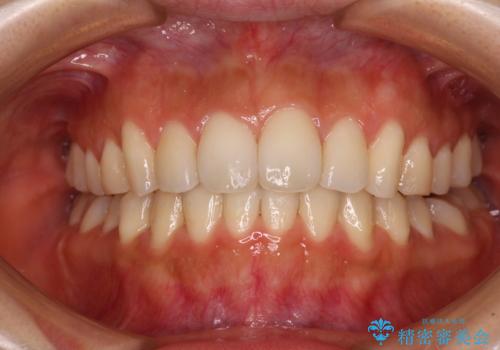

カリエールディスタライザーを併用した、咬み合わせ改善のインビザライン矯正

- 飛び出した前歯と口元の突出感を気にして来院された患者様です。

奥歯の咬み合わせを見ると、上顎が下顎に対して相対的に前方にありました。

口元の突出感を改善するためには、上顎臼歯を後方に移動させた咬み合わせにする必要があります。

インビザライン単体で改善することも可能ですが、達成する可能性が高くないため、カリエールディスタライザーという補助装置を併用して、より確実性を上げることとしました。

奥歯の咬み合わせを改善しながら、並行してインビザラインで歯列を整えることとしました。

カリエールディスタライザーを併用したことで、確実かつ短期間で治療を終えることができました。